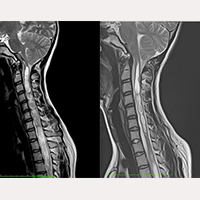

SFT após craniectomía suboccipital

De acordo com as nossas pesquisas, quando se realiza a Craniectomia suboccipital em casos de Síndrome de Arnold Chiari I, se libera a compressão existente no orifício occipital sobre as estruturas nervosas, mas não se elimina a principal causa, que é a tração de todo o sistema nervoso por um Filum terminale mais tenso do que o normal. Por isso, os pacientes operados de Craniectomia suboccipital podem se sentir melhor depois de se submeterem à secção do Filum terminale (SFT).